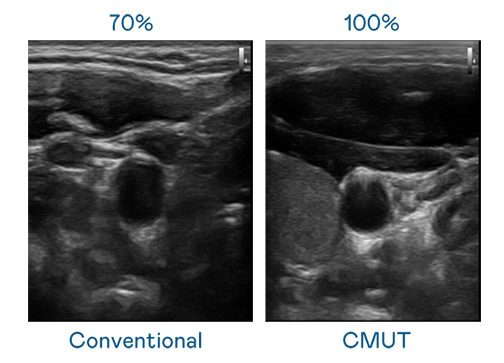

CMUT 技术是一种用电容式微机电元件来产生超音波讯号的技术。与传统 PZT 压电式技术相比,CMUT 频宽增加 30%,更宽频的超音波讯号让影像解析度大幅提升,是实现高影像品质医疗超音波扫描、促进精准医疗发展的关键技术。

大频宽带来超清晰影像

超音波影像的解析度高低,首先取决于探头能发出的讯号频宽。金年会jinnianhui官方在线登录 CMUT 可提供高清晰的超音波讯号,提供高频宽、高灵敏度、影像纹理细节更高的超音波影像,协助医护人员缩短影像判读时间及利用精准的医疗影像进行诊断。